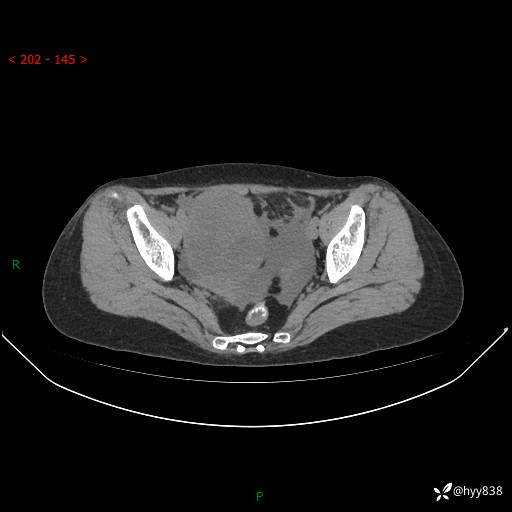

腹盆CT平扫

增强